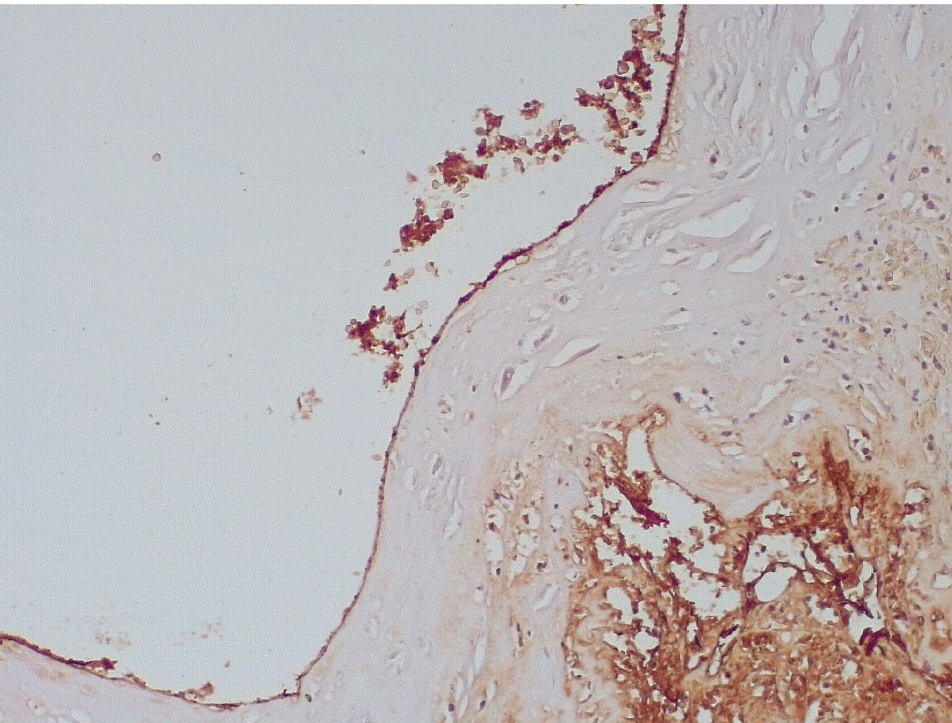

В течение 7–15 суток после стентирования КА наряду с формированием пристеночных фибриновых тромбов с признаками организации в стенках атером наблюдались репаративные процессы, связанные с неоангиогенезом в виде образования мелких тонкостенных кровеносных сосудов капиллярного типа, окруженных мелкими лимфоцитарными, гистиоцитарными клеточными инфильтратами (рис. 6, 7).

Сохранялась резковыраженная яркая экспрессия ФВ как со стороны интимы, так и субинтимально, в участках альтерации атером (рис. 8). В то же время экспрессия белка CD31 была негативной на всем протяжении стенок КА.

Позднее, спустя 3–7 суток, возникают пристеночные смешанные тромбы, которые через 7–15 суток имеют признаки организации, что сопровождается резкой яркой экспрессией белка фактора Виллебранда.